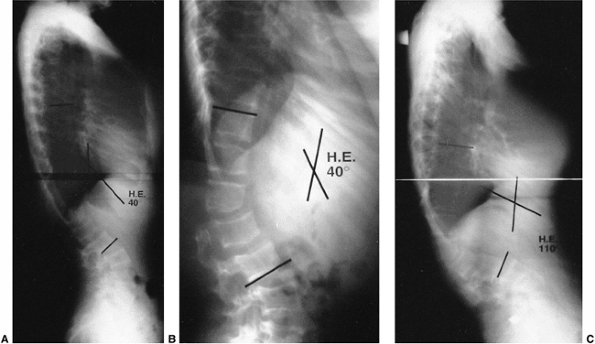

Figure 20.16 A:

Patient with Scheuermann kyphosis has thoracic kyphosis, compensatory lumbar lordosis, anterior protrusion of the head, and rotation of the pelvis. B: Patient with Scheuermann kyphosis in a Milwaukee brace. The placement of the pelvic girdle, posterior thoracic pads, occipital pads, and neck ring encourage correction of the kyphosis. C: Correction of kyphosis after Milwaukee brace treatment. (Courtesy of Robert Winter, MD, Minneapolis.) |

least preventing progression of the kyphotic deformity (82) (Fig. 20.17).

Figure 20.17 A: Lateral radiograph of a 15-year-old girl with a 64-degree thoracic kyphosis secondary to Scheuermann disease. B: Lateral radiograph of the patient in a Milwaukee brace with the kyphotic deformity improved to 39 degrees. C: Lateral radiograph obtained after the patient completed brace treatment; the kyphotic deformity has improved to 33 degrees.